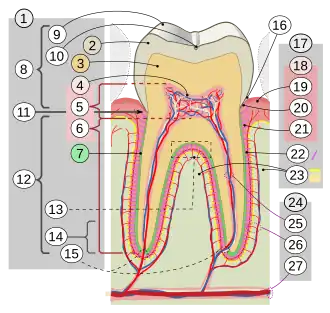

| ||

17. Periodonto 18. Encía: 19. libre o interdental 20. marginal 21. alveolar 22. Ligamento periodontal 23. Hueso alveolar 24. Irrigación e inervación: 25. dental 26. periodontal 27. a través del canal alveolar

Básicamente en el diente se pueden reconocer dos partes, la corona dental, parte recubierta por esmalte dental y la raíz dental no visible en una boca sana.

Tejidos del diente

Esmalte dental: es un tejido formado por hidroxiapatita y proteínas (en muy baja proporción). Es el tejido más duro del cuerpo humano y del mundo. En zonas donde el esmalte es más delgado o se ha desgastado, puede ser sumamente sensible. El esmalte es translúcido, insensible al dolor pues en él no existen terminaciones nerviosas. Con el flúor se forman cristales de fluorhidroxiapatita que es mucho más resistente que la hidroxiapatita al ataque de la caries dental.

Dentina: tejido mineralizado, pero en menor proporción que el esmalte. Es el responsable del color de los dientes. Contiene túbulos en donde se proyectan prolongaciones de los odontoblastos, llamados fribillas de Thomes, las cuales son las causantes de la sensibilidad. Las propiedades físicas de la dentina son: Color, radiopacidad, traslucidez, elasticidad, dureza y permeabilidad.

Cemento radicular: tejido conectivo altamente especializado. Es una capa dura, opaca y amarillenta que recubre la dentina a nivel de la raíz del diente. Se encarga de unir al órgano dentario con el hueso alveolar a través del ligamento periodontal.

Pulpa dental: tejido mesodérmico está constituida por un tejido suave que contiene vasos sanguíneos (arteria y vena) que conducen la sangre hacia el diente y por fibras nerviosas que otorgan sensibilidad al diente. Dichos nervios atraviesan la raíz (del diente) por medio de finos canales. Su célula principal son los odontoblastos (son células tanto de la pulpa como de la dentina), estos fabrican dentina y son los que mantienen la vitalidad de la dentina. Los odontoblastos poseen prolongaciones conocidas como Procesos Odontoblásticos o fribillas de Thomes, que se alojan en los túbulos dentinarios. Junto con la dentina forma el órgano dentino-pulpar.

En la pulpa dentaria se encuentra alojado el paquete vasculo nervioso que está formado por un filete nervioso, una vena y una arteria, dándole la irrigación e inervación necesaria. Las actividades funcionales de la pulpa son: Inductora de la temperatura, formativa, nutritiva, sensitiva, defensiva y reparadora.

Periodonto:Conjunto de ligamentos que fijan el diente dentro del alveolo óseo del maxilar. Básicamente son las estructuras que dan soporte y sustentabilidad al diente.

Encía: es la parte de la mucosa bucal que rodea el cuello de los dientes y cubre el hueso alveolar.

Ligamento periodontal: es una estructura del tejido conjuntivo que rodea la raíz y la une al hueso alveolar. Entre sus funciones están la inserción del diente al hueso alveolar y la resistencia al impacto de los golpes. También posee propiedades mecanorreceptoras siendo capaz de transmitir las fuerzas ejercidas sobre el diente a los nervios adyacentes.

Cemento dentario: es la estructura mineralizada que cubre la dentina radicular, compensa el desgaste fisiológico en la erupción pasiva y sobre todo, la inserción a las fibras de la encía y del ligamento periodontal.

Hueso alveolar: es la parte del hueso maxilar y mandíbula donde se alojan los dientes. Se denomina hueso alveolar al hueso de los maxilares y mandíbula que contiene o reviste las cuencas o procesos alveolares, en las que se mantienen las raíces de los dientes.

- Corona: es la parte del diente que está recubierta por esmalte. Podemos observar en la boca la parte funcional del órgano dentario. Esta porción del diente se encuentra expuesta al medio bucal en forma permanente.

- Cuello: llamado zona cervical, es la unión de la corona con la raíz y se sitúa en la encía marginal.

- Raíz: esta parte del diente no es visible en la cavidad bucal ya que está incrustada en el proceso alveolar, dentro del hueso, y se encuentra recubierta por el cemento dentario. Sirve de anclaje. Los dientes normalmente tienen entre una y tres raíces, dependiendo de si son incisivos (una raíz), caninos (1), premolares (1 o 2) o molares (dos o tres, en casos excepcionales más de tres)